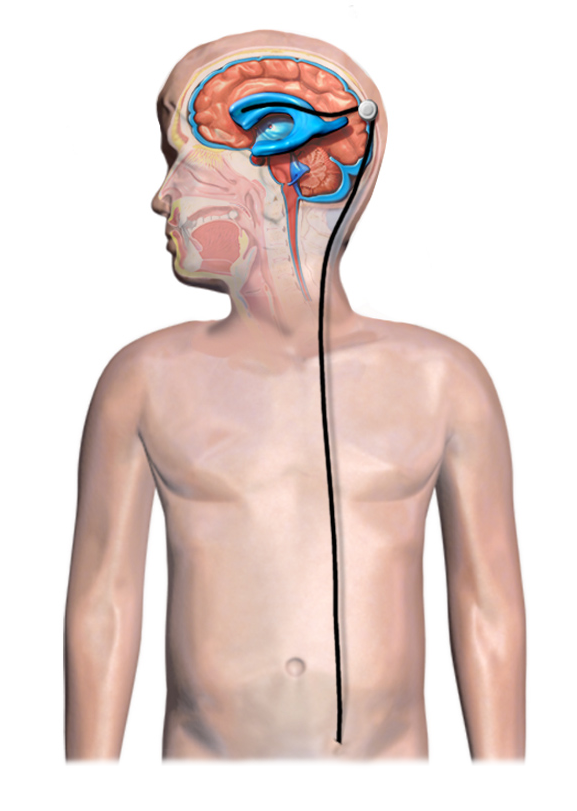

A diagram of typical shunt installation in a child with hydrocephalus. Image credit: Blausen Medical Communications via Wikimedia Commons (CC BY-SA 4.0), edits by Rachel Lense for The Science Writer

While there are different types of shunts, all work with the same three parts: the ventricular catheter in the brain, which Lily has always called her “bumps,” and a valve that connects it to a long piece of spaghetti-like tubing that extends down along the right side of her neck and into her abdominal cavity, where the excess CSF is drained and absorbed. On her stomach, Lily has two scars — tally marks from the original shunt insertions. On her head, she has four: two to match her belly and two more for the two shunt revisions.

It is the ventricular catheter that most often fails, especially in pediatric patients, according to Carolyn Harris, Ph.D., associate professor of chemical engineering and materials science at Wayne State University in Detroit; however, the mechanisms that lead to failure are not totally understood.